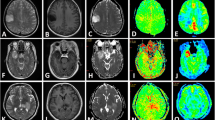

Fifty-six patients with radiologically suspected untreated glioma were studied with T1- and T2-weighted MR imaging, dynamic contrast-enhanced MR imaging, diffusion tensor imaging, and volumetric whole-brain MR spectroscopic imaging. Receiver-operating characteristic analysis was performed using the relative cerebral blood volume (rCBV), apparent diffusion coefficient, fractional anisotropy, and multiple spectroscopic parameters to determine optimum thresholds for tumor grading and to obtain the sensitivity, specificity, and positive and negative predictive values for identifying high-grade gliomas. Logistic regression was performed to analyze all the parameters together.

The rCBV individually classified glioma as low and high grade with a sensitivity and specificity of 100 and 88 %, respectively, based on a threshold value of 3.34. On combining all parameters under consideration, the classification was achieved with 2 % error and sensitivity and specificity of 100 and 96 %, respectively.

Individually, CBV measurement provides the greatest diagnostic performance for predicting glioma grade; however, the most accurate classification can be achieved by combining all of the imaging parameters.